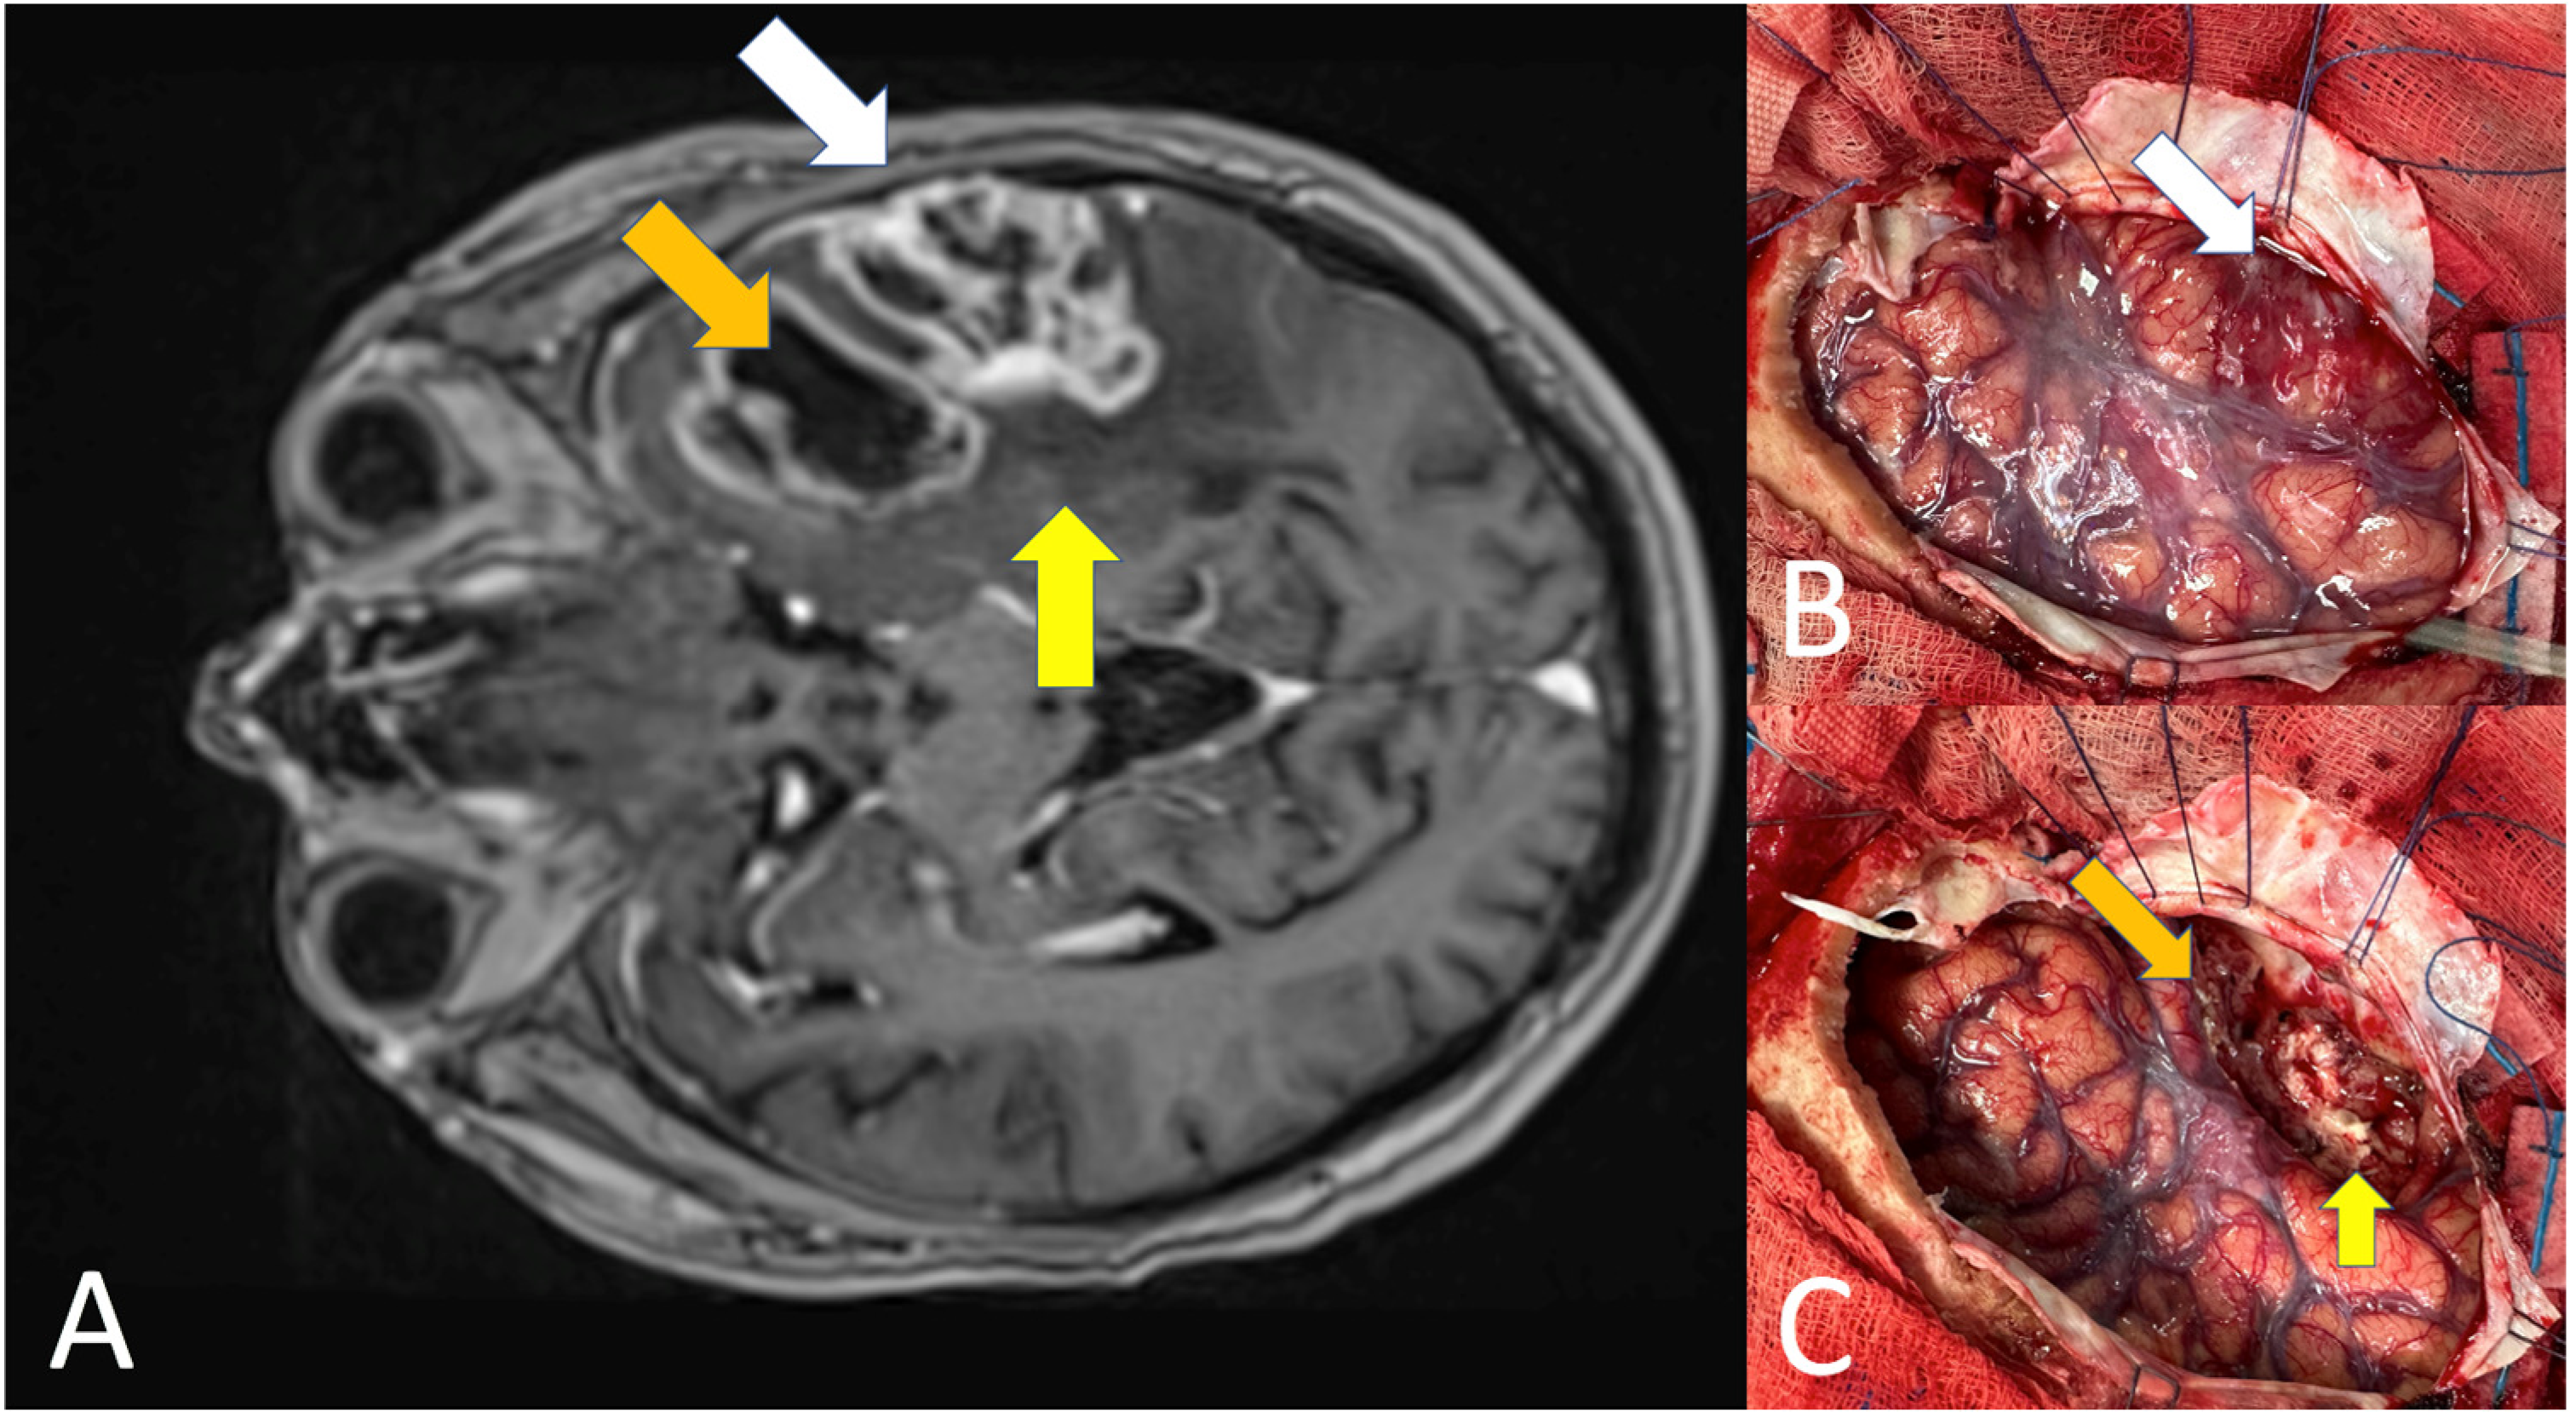

- Altieri, R.; Broggi, G.; Certo, F.; Pacella, D.; Cammarata, G.; Maione, M.; Garozzo, M.; Barbagallo, D.; Purrello, M.; Caltabiano, R.; et al. Anatomical Distribution of Cancer Stem Cells between Enhancing Nodule and FLAIR Hyperintensity in Supratentorial Glioblastoma: Time to Recalibrate the Surgical Target? Neurosurg. Rev. 2022, 45, 3709–3716. [Google Scholar] [CrossRef]

- Altieri, R.; Certo, F.; Pacella, D.; Cammarata, G.; Garozzo, M.; Broggi, G.; Caltabiano, R.; Magro, G.; Russo, G.; Cosentino, S.; et al. Metabolic Delineation of IDH1 Wild-Type Glioblastoma Surgical Anatomy: How to Plan the Tumor Extent of Resection. J. Neurooncol. 2023, 162, 417–423. [Google Scholar] [CrossRef]

- Broggi, G.; Altieri, R.; Barresi, V.; Certo, F.; Barbagallo, G.M.V.; Zanelli, M.; Palicelli, A.; Magro, G.; Caltabiano, R. Histologic Definition of Enhancing Core and FLAIR Hyperintensity Region of Glioblastoma, IDH-Wild Type: A Clinico-Pathologic Study on a Single-Institution Series. Brain Sci. 2023, 13, 248. [Google Scholar] [CrossRef]

- Altieri, R.; Barbagallo, D.; Certo, F.; Broggi, G.; Ragusa, M.; Di Pietro, C.; Caltabiano, R.; Magro, G.; Peschillo, S.; Purrello, M.; et al. Peritumoral Microenvironment in High-Grade Gliomas: From FLAIRectomy to Microglia-Glioma Cross-Talk. Brain Sci. 2021, 11, 200. [Google Scholar] [CrossRef]